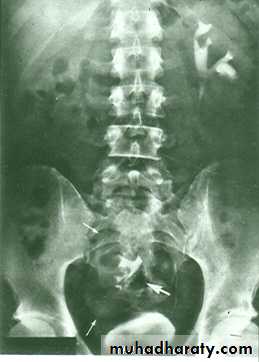

The urinary bladder is located at low position , the plain x-ray shows wide separation of symphysis pubis

ECTOPIA VESICA